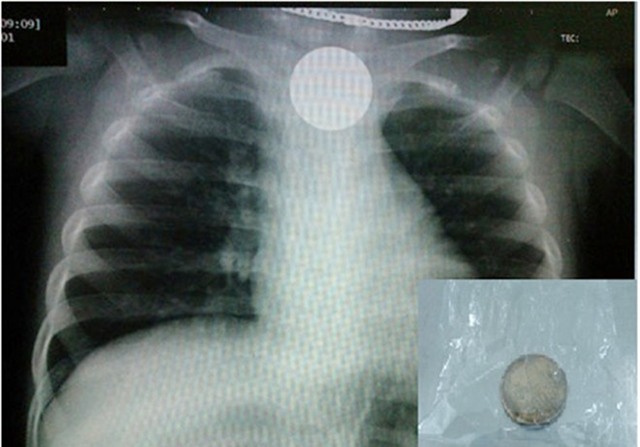

Tấm phim chụp X-Quang cho thấy đồng xu rơi xuống thực quản của trẻ. Ảnh minh họa. |